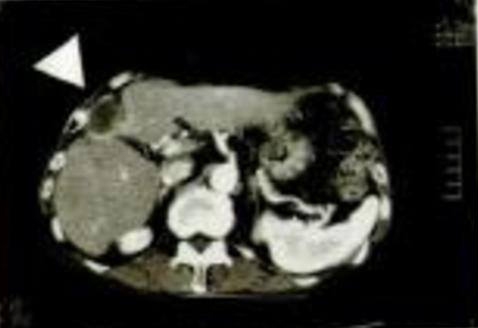

Imaginea CT stânga a fost luată în a 11-a lună de la

inițierea ingerării Agaricus.

Contrar declarației medicului curant, care susținea că mai are 3 luni de viață, imaginea de față indică o reducere majoră a zonei afectate de cancer.

Mărimea acesteia este de 33 mm x 24 mm. La măsurarea volumului s-a constatat o reducere de 30 de ori. În plus, au existat o serie de cazuri în care s-a considerat că Oyama Agaricus și-a manifestat eficacitatea și în mod separat. În multe cazuri, s-a apreciat că a sporit efectul terapeutic în tratamentul concomitent cu radioterapie și chimioterapie.